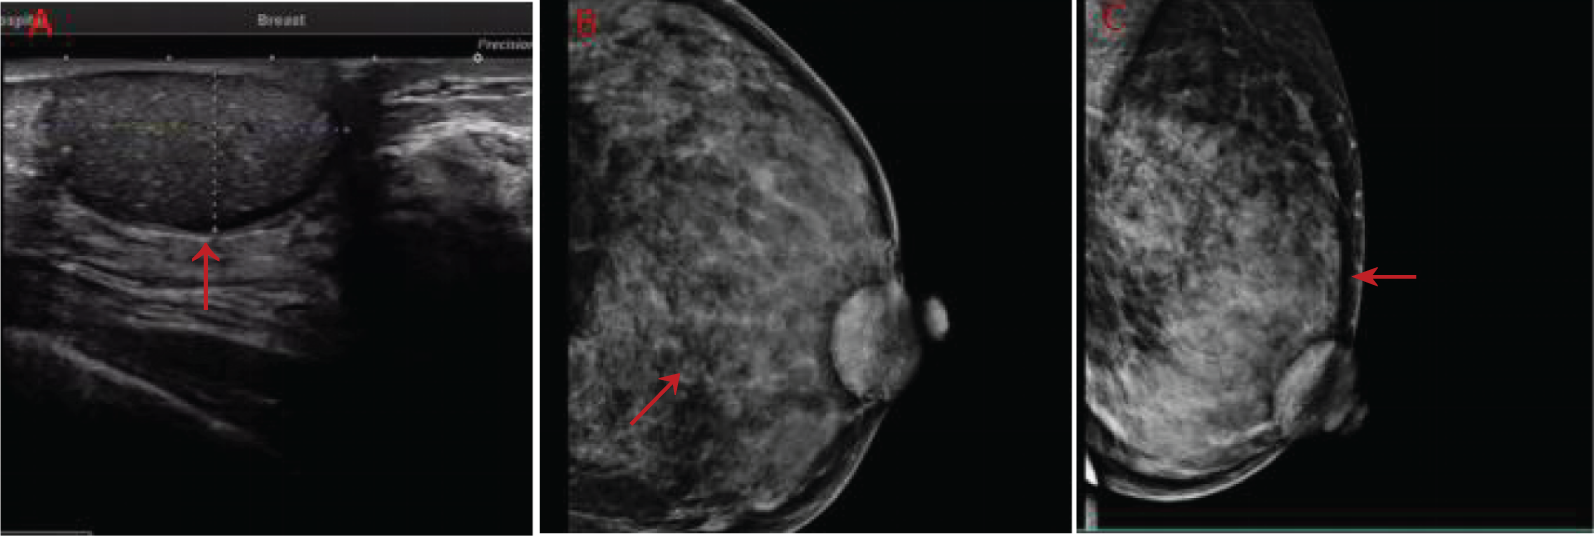

A 50-year-old woman with a mass near the left nipple was admitted on 3 January 2022. Four months before, the patient accidentally found the mass near the left nipple. The mass had a soft texture and poor mobility. It was approximately 2.0 × 2.0 cm in size and showed no swelling, pain, or ulceration. It was left without any treatment. In the past 2 months, the patient visited our hospital, and the size of the mass had increased to approximately 3.0 × 3.0 cm (Figure 1). The patient had no history of surgery and trauma and had a normal menstrual history. There was no remarkable personal or family history. Physical examination showed left–right breast asymmetry, with the left breast slightly greater than the right one. None of the breasts showed skin redness, orange peel signs, nipple depression, or dimpling. The bulge of the mass was visible in the left nipple areola area and was seriously adherent and not mobile. A mass of approximately 3.0 × 3.0 cm was palpable directly behind the left nipple and areola area. It was soft, with a clear boundary and poor mobility on palpation. No significant mass was palpable in the right mammary gland. No enlarged lymph nodes were found in the bilateral axillary and supraclavicular regions. Color Doppler ultrasound examination revealed a low echo mass measuring 3 cm × 1.5 cm on the inner side of the left breast nipple, with a clear boundary and regular morphology, strong echo light spots, and blood flow signal around the periphery. Based on ultrasound, a diagnosis of left breast mass BI-RADS 4 class 4a was made (Figure 2A). Molybdenum target mammography revealed an isodense mass with a clear margin in the left areola area. There was no obvious mass and suspicious calcification in the right breast. In both breasts, skin and nipple shadows were normal. Mammography diagnosis was a mass in the left areola area: BI-RADS 4A (Figures 2B, C). In the punctured tissue, there were a lot of cuticular samples, a little dermal collagen-like tissue, and a few broken squamous epithelium cells, so an epidermoid cyst was considered. The preoperative diagnosis was a breast epidermoid cyst. Local extended resection of the mass of the nipple was conducted, and the operation went smoothly. However, during the resection, it was found that the internal soybean residue-like substance involved a larger area than what was seen on actual imaging with a foul odor. In order to remove it completely and reduce the risk of recurrence, we had to remove a larger area to ensure the safety of oncology. A general overview of the postoperative specimens is shown in Figure 3: a volume measuring 11 cm × 6.5 cm × 2 cm with a skin area of 11 cm × 6.5 cm and a nipple diameter of 1.7 cm; adjacent to the skin, a cystic mass with a volume of 2.5 cm × 2.5 cm × 1.5 cm was seen with a tofu-like residue and a suspicious sinus tract. Microscopic assessment (Figure 4) revealed an epidermoid cyst, a local rupture with a foreign body giant cell reaction and a secondary inflammatory reaction, and a local large neutrophil infiltration with the formation of microabscess. The postoperative pathological evaluation confirmed an epidermoid cyst in the left breast. The patient recovered well after surgery and had annual breast color ultrasound and molybdenum target mammography of the surgical site. After 2 years of postoperative follow-up, the patient had no associated complications and no signs of tumor recurrence.

Figure 2

(A) Color ultrasonography evaluation of the patient before surgery. (B, C) Preoperative images using molybdenum target mammography (red arrows indicate lesions).